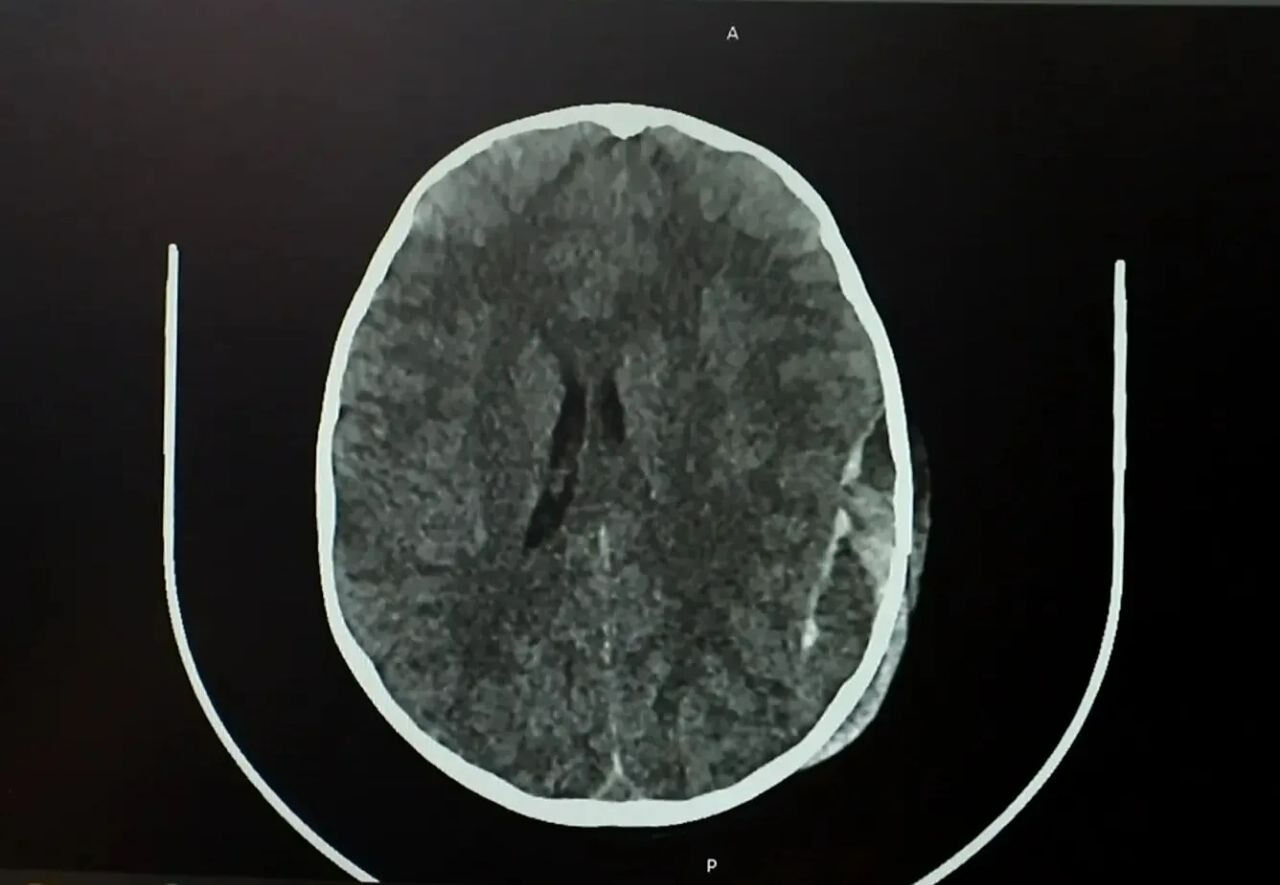

Как сообщает Минздрав Кузбасса, сразу после происшествия у ребёнка не было видимых травм головы, однако на следующий день он начал отказываться от еды. Родители обратились в больницу, где обследование выявило серьёзные повреждения – перелом черепа и острую эпидуральную гематому.

Мальчика экстренно доставили в операционную. Нейрохирурги провели сложную операцию – костно-пластическую трепанацию черепа, удалили гематому и остановили кровотечение.